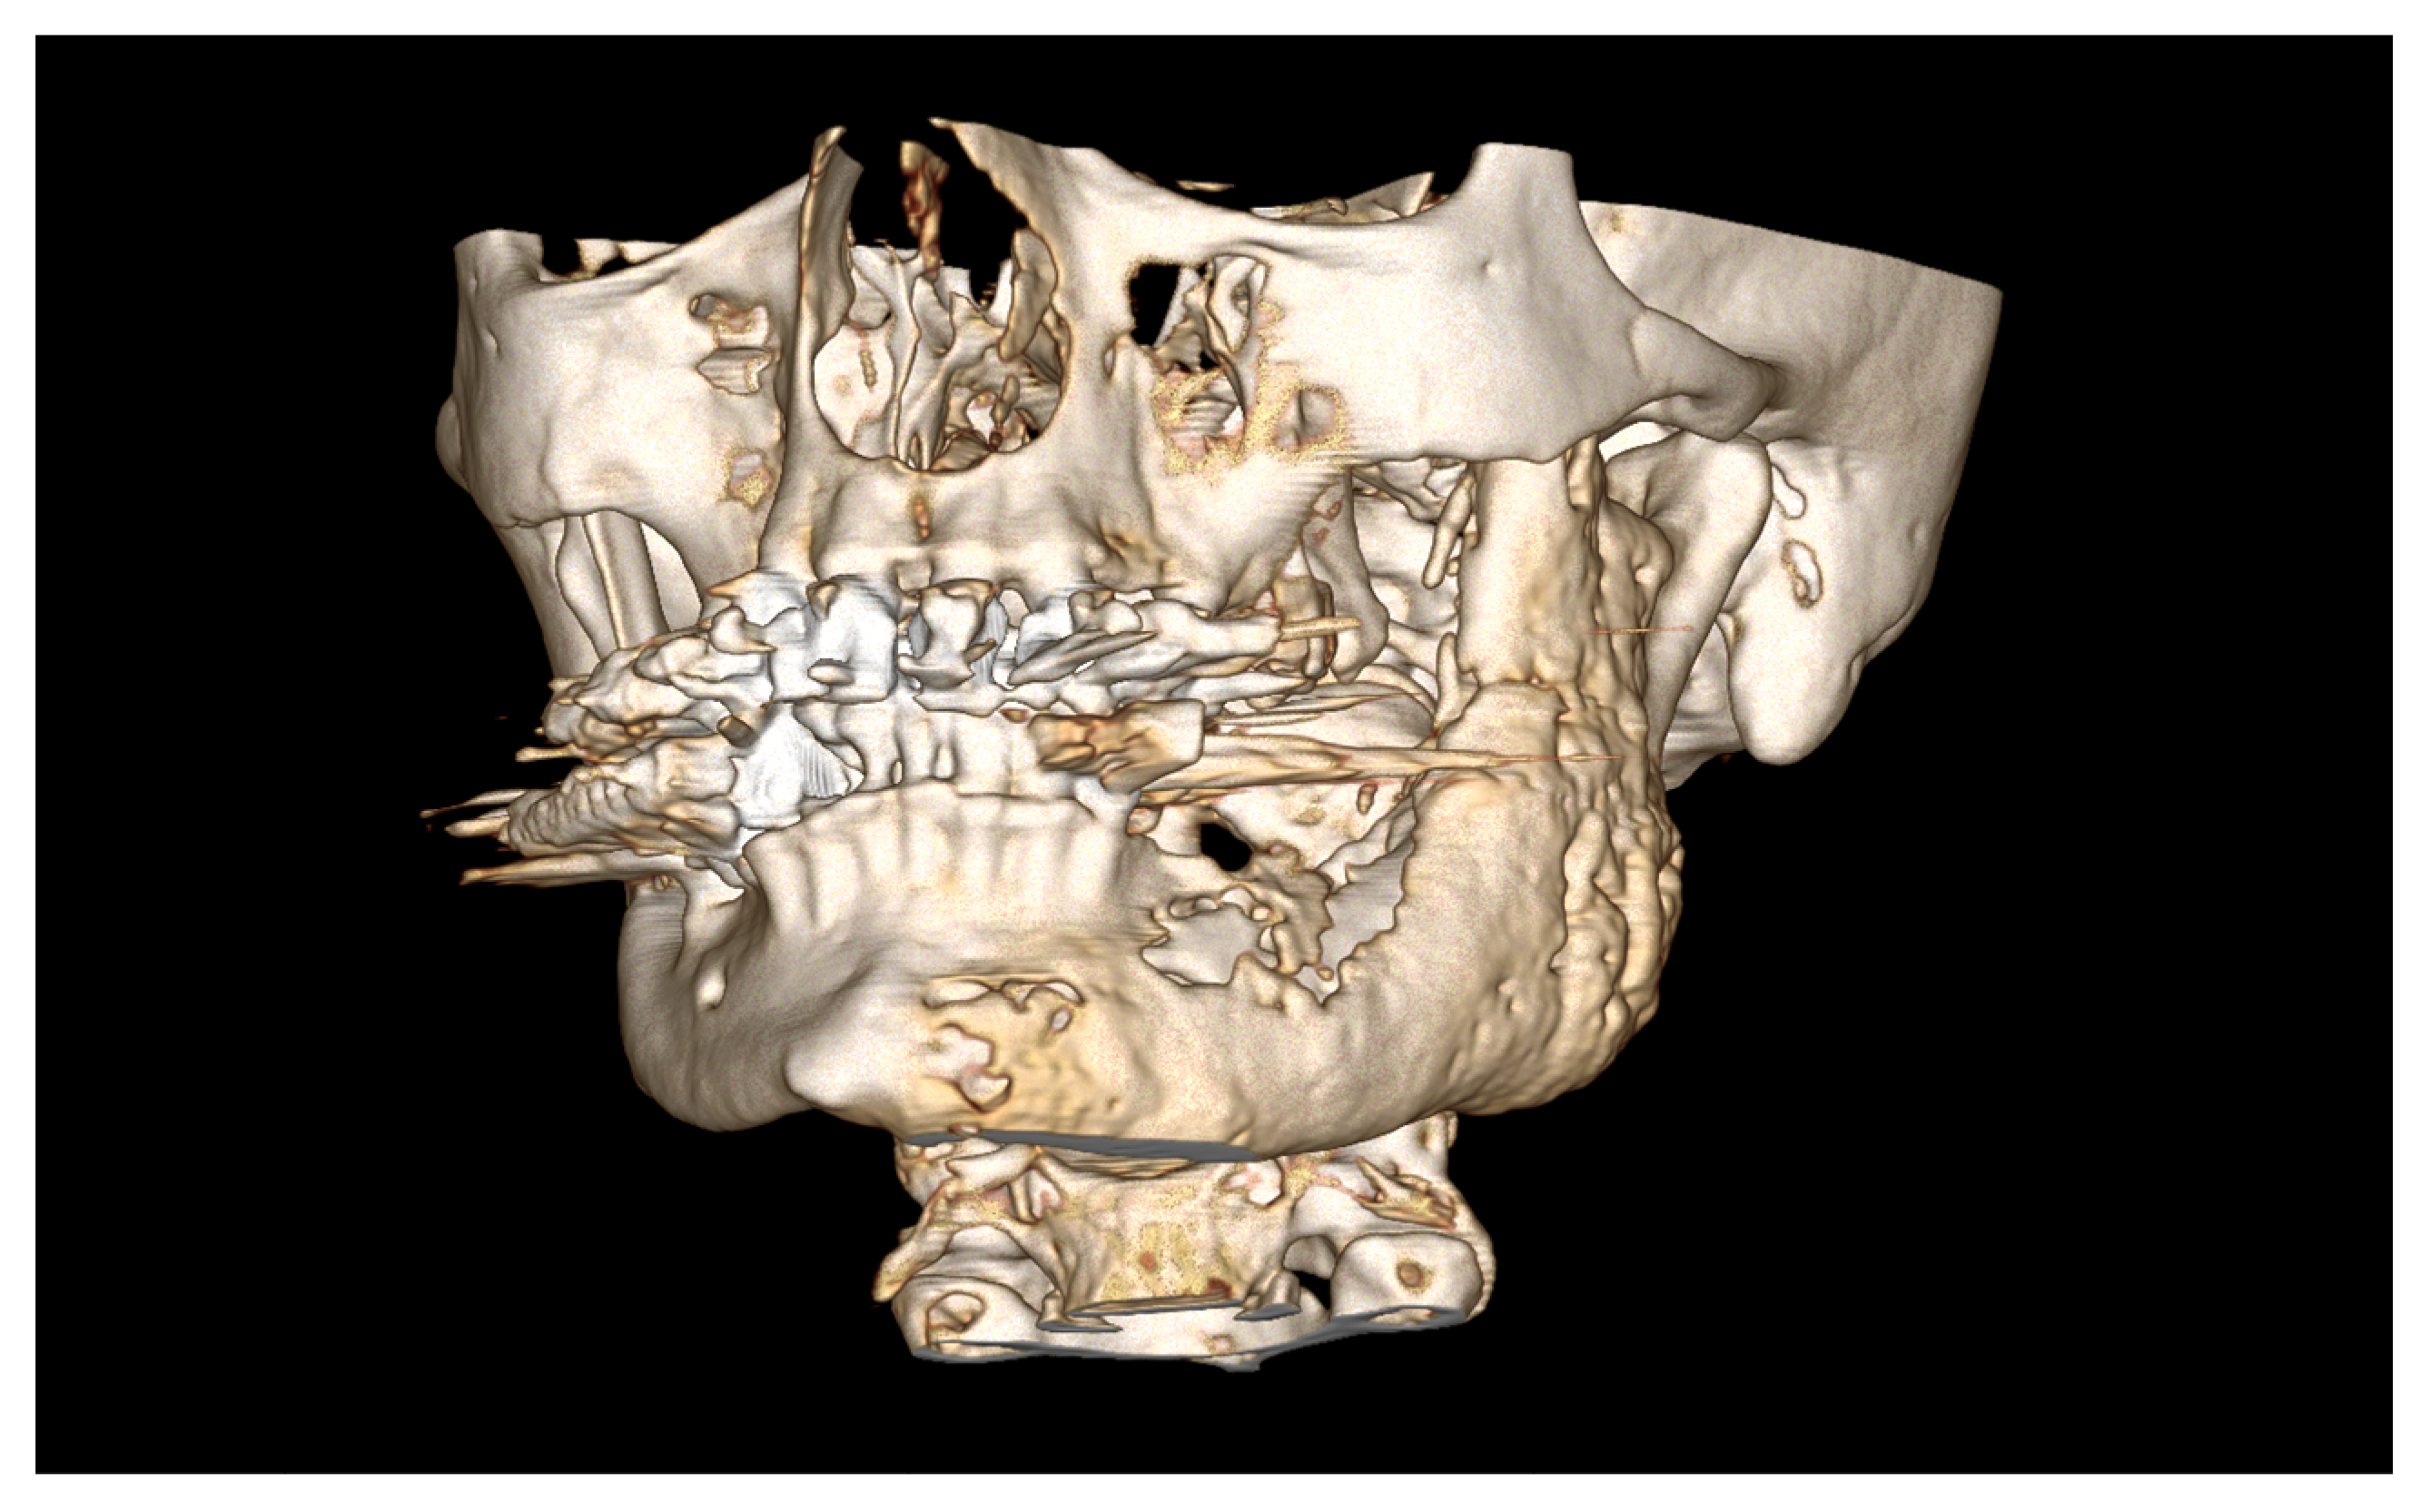

| September 2022: | Partial mandibular resection from the left mandibular angle to the right mandible, including the right temporomandibular joint, CAD/CAM-guided reconstruction with a bilateral free scapula flap with skin island, and patient-specific plate. In the course:

| April 2020: | Partial mandibular resection from the left to the right mandibular angle, CAD/CAM-assisted reconstruction using a free fibular graft and PSI, temporary tracheostomy. In the course: development of aspiration pneumonia treated with piperacillin and tazobactam 4.5 g for 8 days. |